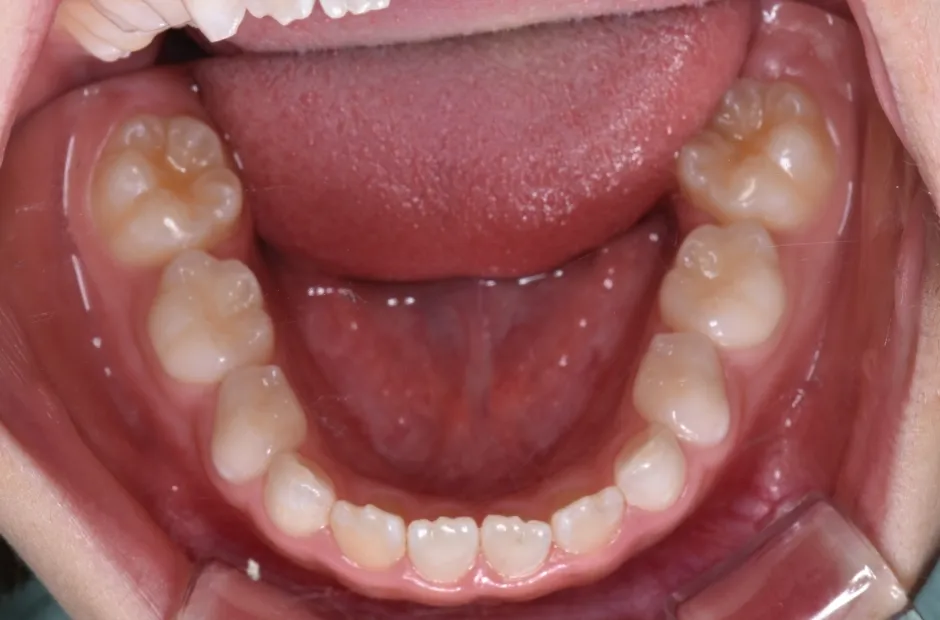

舌側弧線装置(タングクリブ付)

開咬、すきっ歯

| 診断名・主訴 | 開咬、すきっ歯 |

|---|---|

| 年齢・性別 | 7歳・男性 |

| 治療期間・回数 | 3年 |

| 治療に用いた主な装置 | 舌側弧線装置(タングクリブ付) |

| 抜歯部位 | なし |

| 治療費 | 30万円(税抜) |

| リスク・副作用 | 装置による違和感・疼痛・歯肉退縮・歯根吸収・虫歯のリスクなど |

治療前

治療後